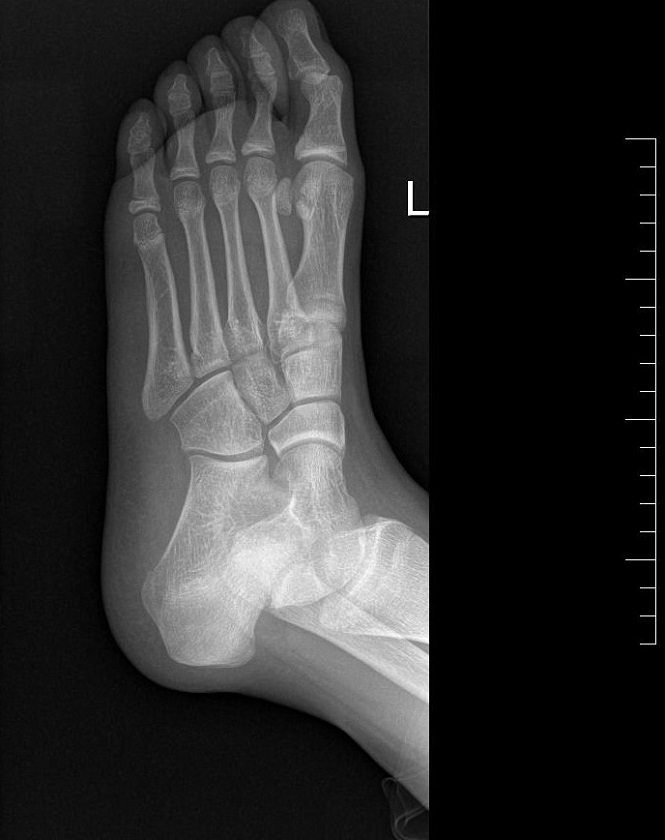

Paciente de 11 años que acude a Urgencias por dolor en el pie izquierdo de 6 meses de evolución, junto con inflamación de este en las últimas 24 horas. No guarda relación con traumatismo ni con sobreesfuerzo físico. A la exploración física, presenta dolor a la palpación en la articulación metatarsofalángica del primer dedo, con movilidad conservada. Se realiza radiografía de la extremidad (Figuras 1 y 2).

Figura 2. Radiografía ósea oblicua de pie izquierdo. Se visualizan, de forma lateral, las mismas tres estructuras bien delimitadas.